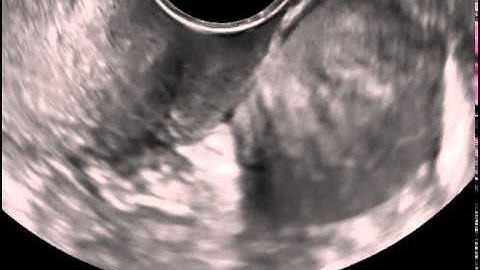

VPFW GYN Urodynamics Web Movie 2014